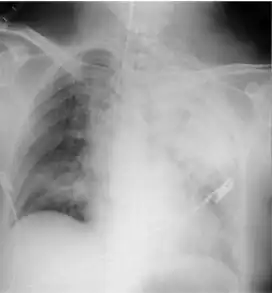

Mendelson's syndrome is characterised by a bronchopulmonary reaction following aspiration of gastric contents during general anaesthesia due to abolition of the laryngeal reflexes. The main clinical features are signs of general hypoxia, two to five hours after anaesthesia. Such features may include cyanosis, dyspnea, fever, pulmonary wheeze, crepitant rales, rhonchi, and tachycardia with a low blood pressure. Decreased arterial oxygen tension is also likely to be evident. Pulmonary edema can cause sudden death or death may occur later from pulmonary complications.

- Radiographic film